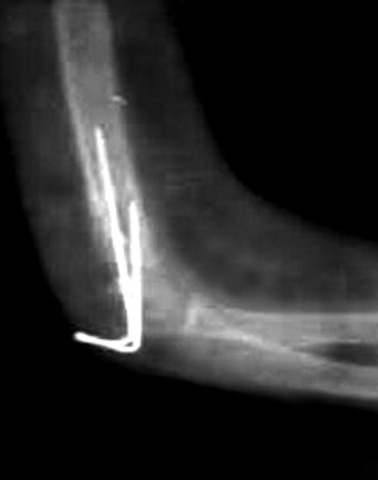

• Primera fractura

Primera fractura

Fue en el codo del brazo izquierdo, en el colegio una niña me empujo del pasamanos y caí sobre el brazo, estos pasamanos estaban ubicados en la parte de atrás de coordinación

• Segunda Fractura

Segunda Fractura

Me astille el hueso del brazo izquierdo jugando, yo estaba corriendo persiguiendo a un amigo, el tumbo un recogedor y me enrede el brazo cayó sobre el filo del recogedor

• Tercera fractura

Tercera fractura

Tambien en el brazo izquierdo jugando microfutbol en el colegio Amaya me hizo caer encima del brazo al llegar a la Clinica los medicos se dieron cuenta que tambien tenia fracturado el pie izquierdo